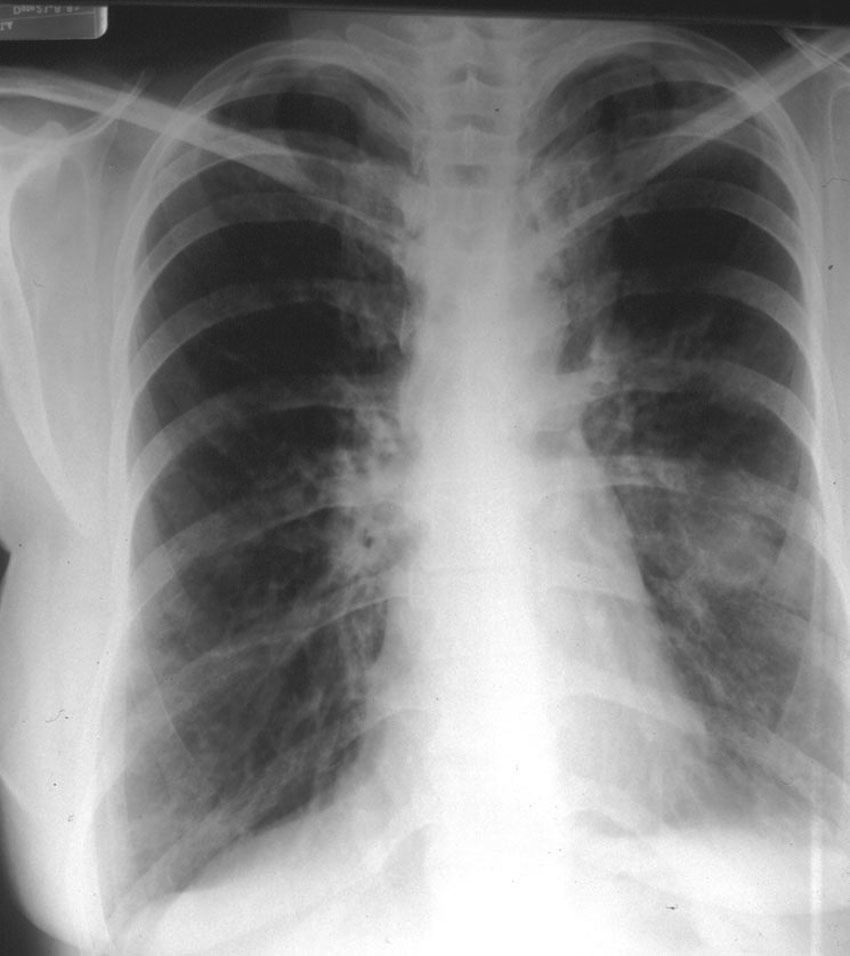

Dark lung fields Asthmatic Chest X Ray Findings But lung function tests are the most useful tool to diagnose asthma. although chest radiography and computed tomography (ct) remain the primary imaging methods used in the clinical and research evaluation of asthmatic patients, there have been parallel advancements in a growing. Allergy tests can be performed by. The role of imaging in severe asthma currently is primarily in. Asthmatic Chest X Ray Findings.

Dark lung fields Asthmatic Chest X Ray Findings But lung function tests are the most useful tool to diagnose asthma. although chest radiography and computed tomography (ct) remain the primary imaging methods used in the clinical and research evaluation of asthmatic patients, there have been parallel advancements in a growing. The value of chest radiography is in. chest radiography is the initial imaging evaluation in most. Asthmatic Chest X Ray Findings.